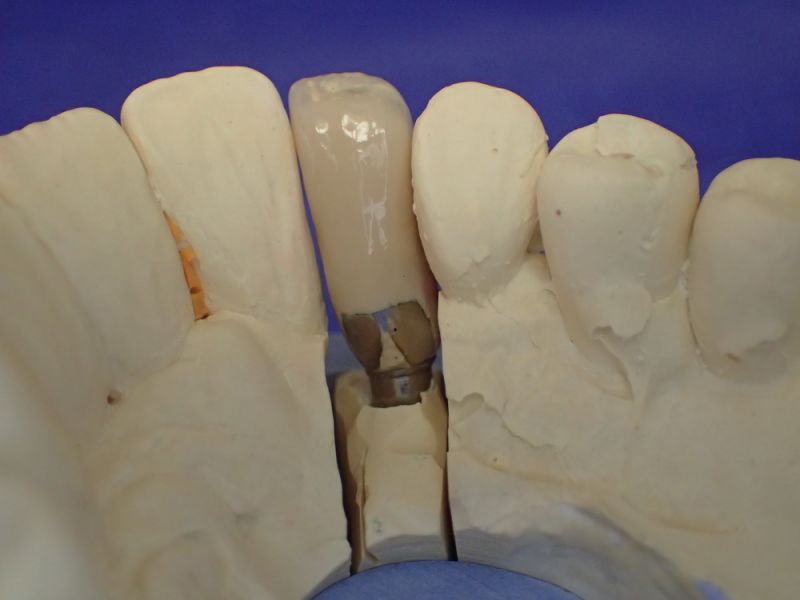

Kieler Patient erhält implantatgestützte Kronenversorgung 22

Dieser Patient ist gesetzlich krankenversichert und hat sich nach und nach inzwischen im CMD CENTREUM KIEL 10 Implantat inserieren lassen.

In diesem Fall wäre es sogar möglich gewesen auf das neue Implantat 22 zu verzichten und eine Versorgung auf den vorhandenen Implantaten zu begründen.

Das hätte aber zu einem wesentlich höheren wirtschaftlichen Aufwand geführt, weil die dann notwendige Prothetik, die von den Implantaten hätte entfernt und nachfolgend wieder neu hätte erstellt werden müssen, wesentlich teurer gekommen wäre, als ein neues Implantat mit einer neuen Krone darauf.